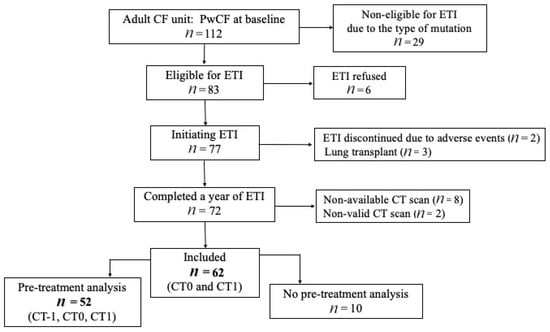

Of the 112 patients managed at the CF center between December 2021 and November 2022, 83 were deemed eligible for ETI by the pulmonologist. After excluding 21, a total of 62 adults with CF (35 males) met the inclusion criteria (Figure 1). The median age at the initiation of ETI was 30.4 (±7.87) years, and 54.8% harbored a heterozygous mutation. The demographic and clinical characteristics of the study cohort are summarized in Table 1.

Figure 1.

Study flow chart. CF: cystic fibrosis. ETI: elexacaftor–tezacaftor–ivacaftor. PwCF: people with cystic fibrosis.